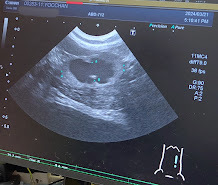

🐈エコー検査では相変わらず肥大したままの腎盂。🐈

他の猫ちゃんはこの腎盂の黒い部分が大体どのくらいの大きさなんですか?と先生に聞いたら、

通常は全体が白く写るもので黒く写ってること自体おかしいんですよ。と言われた😱ソウナノ?🐈

ヨッちゃんは専門の動物病院で腎盂腎炎を診てもらった時に、腎臓と膀胱をつなげる手術をしたため尿管が短くなっていて尿路感染を繰り返しやすい体の状態になっていること、尿路感染を繰り返し起こしていると腎臓に膿が溜まってしまう可能性があり、そうなってしまったらSUBシステムの手術(膀胱と腎臓に人工の管を繋げる)の選択肢も消えて、腎臓の摘出手術をしないといけなくなるんですと説明を受けているのもあり、尿の培養検査と薬の感受性検査をするため外注検査に出すことになりました。検査結果は10日ほどかかるので今、結果待ちのところです。